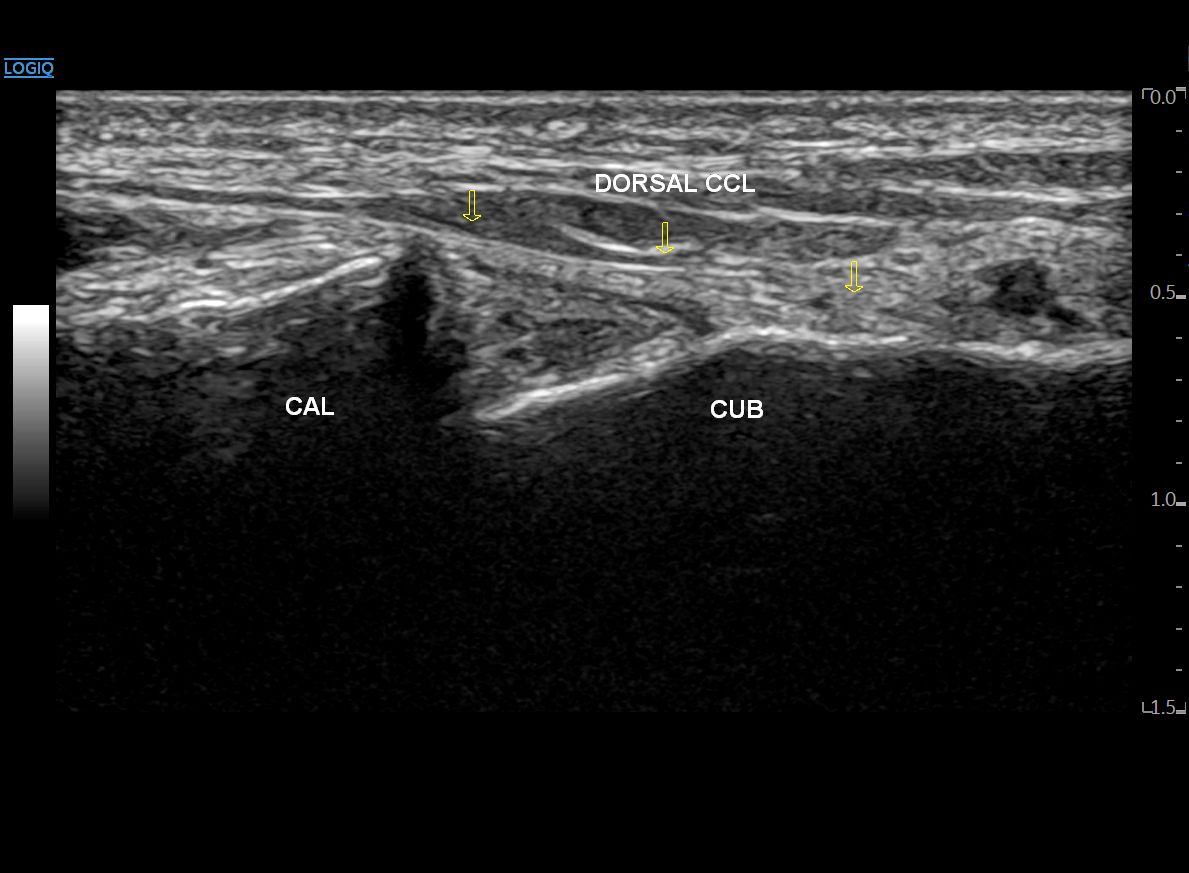

이분인대를 향해 프로브를 내측으로 이동하면

두 뼈를 연결하는 등쪽 종입방인대(Dorsal CCL)가 보이고요.

그 위로 짧은 발가락 폄근이

(단지신근, EDB, Extensor Digitorum Brevis)

보이기 시작합니다.